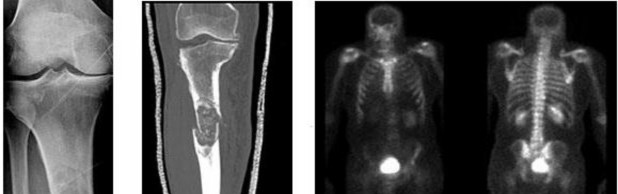

A 15-year-old male presents with deep knee pain awakening him at night. Radiographs show a permeative destructive lesion in the distal femoral metaphysis with a 'sunburst' periosteal reaction and Codman's triangle.

Biopsy confirms high-grade conventional osteosarcoma. What is the most critical prognostic factor for long-term overall survival in this patient?

Explanation

For localized high-grade osteosarcoma, the most important prognostic indicator is the histologic response to neoadjuvant chemotherapy. This is evaluated during the definitive resection. A 'good response' is typically defined as greater than 90% or 99% tumor necrosis. Patients who achieve this level of necrosis have a significantly improved disease-free and overall survival rate compared to 'poor responders' who have extensive viable tumor cells remaining.